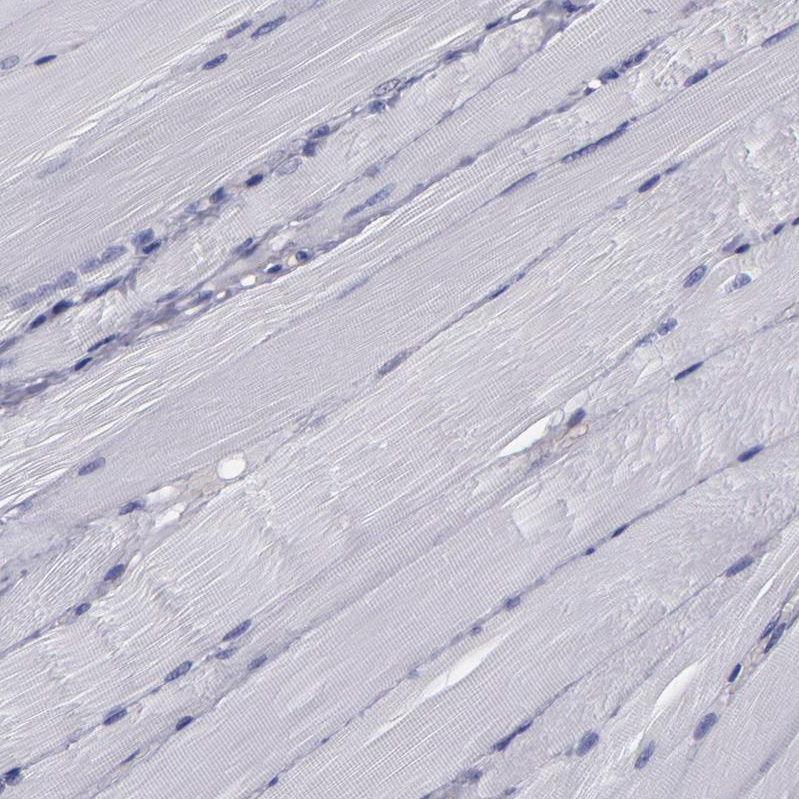

Immunohistochemistry analysis in human cerebral cortex and skeletal muscle tissues using HPA002384 antibody. Corresponding CARS RNA-seq data are presented for the same tissues.